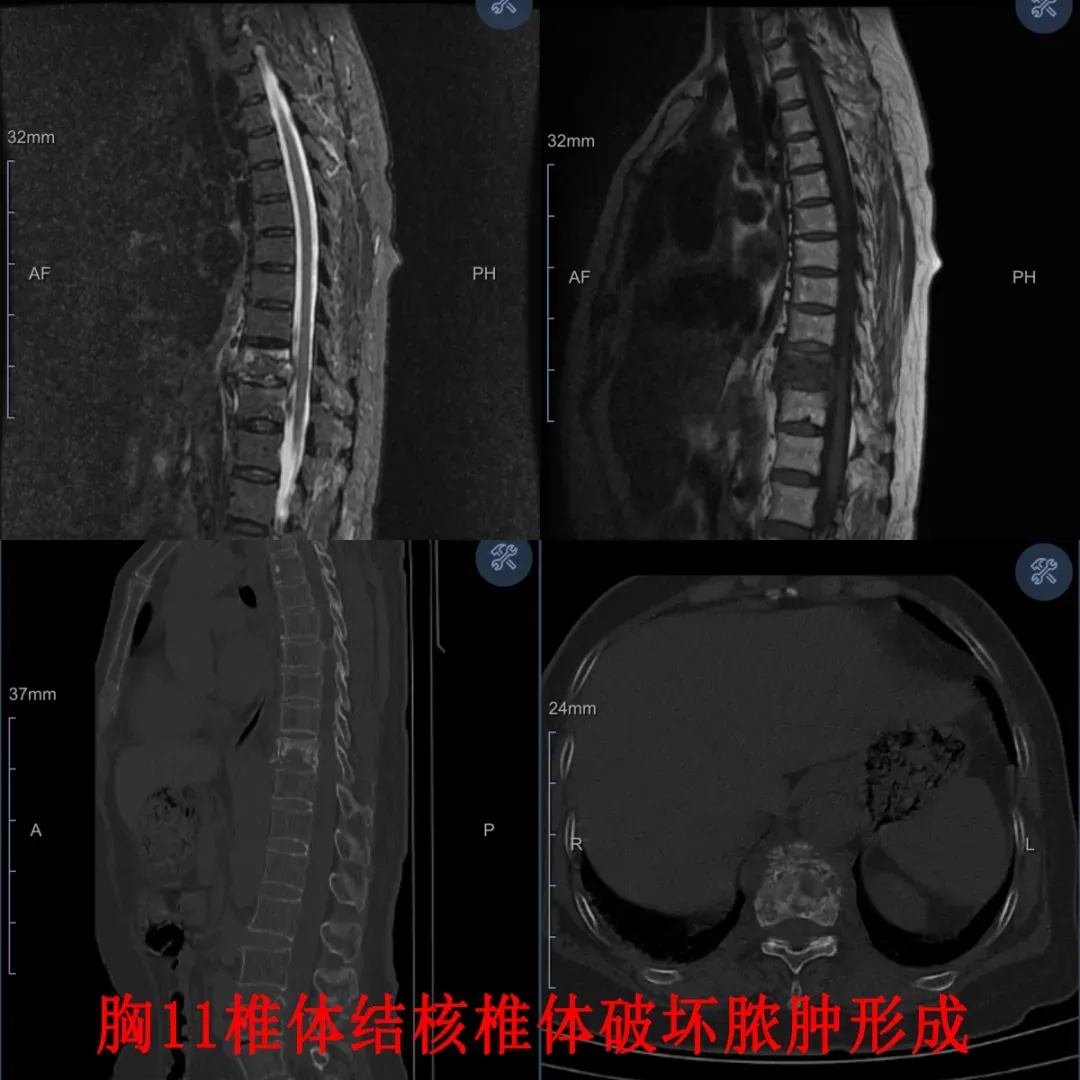

患者为67岁女性,因不明原因发热、胸背部疼痛就诊,确诊肺结核后经规范抗结核治疗,胸背痛却持续加重,无法平卧,已3个月未能下地,严重影响生活质量。来到延大附院就诊后,经脊柱外科刘军副主任医师初步诊断,患者为胸椎结核,考虑到患者病程超半年、卧床2月余,全身消耗严重、体质极差,常规开放手术创伤和风险极大,并发症率较高,经脊柱外科全体人员积极讨论协商,最终确定将双侧入路脊柱内镜下微创病灶清除、植骨融合与徒手经皮微创长节段椎弓根螺钉内固定技术相结合,开展全微创脊柱结核治疗。

内镜下病灶清除

该手术创伤小、出血少、恢复快,既能彻底清除结核病灶,又能精准稳定脊柱,最大限度保护正常组织,显著降低手术风险,为体质较差患者提供安全有效的解决方案。